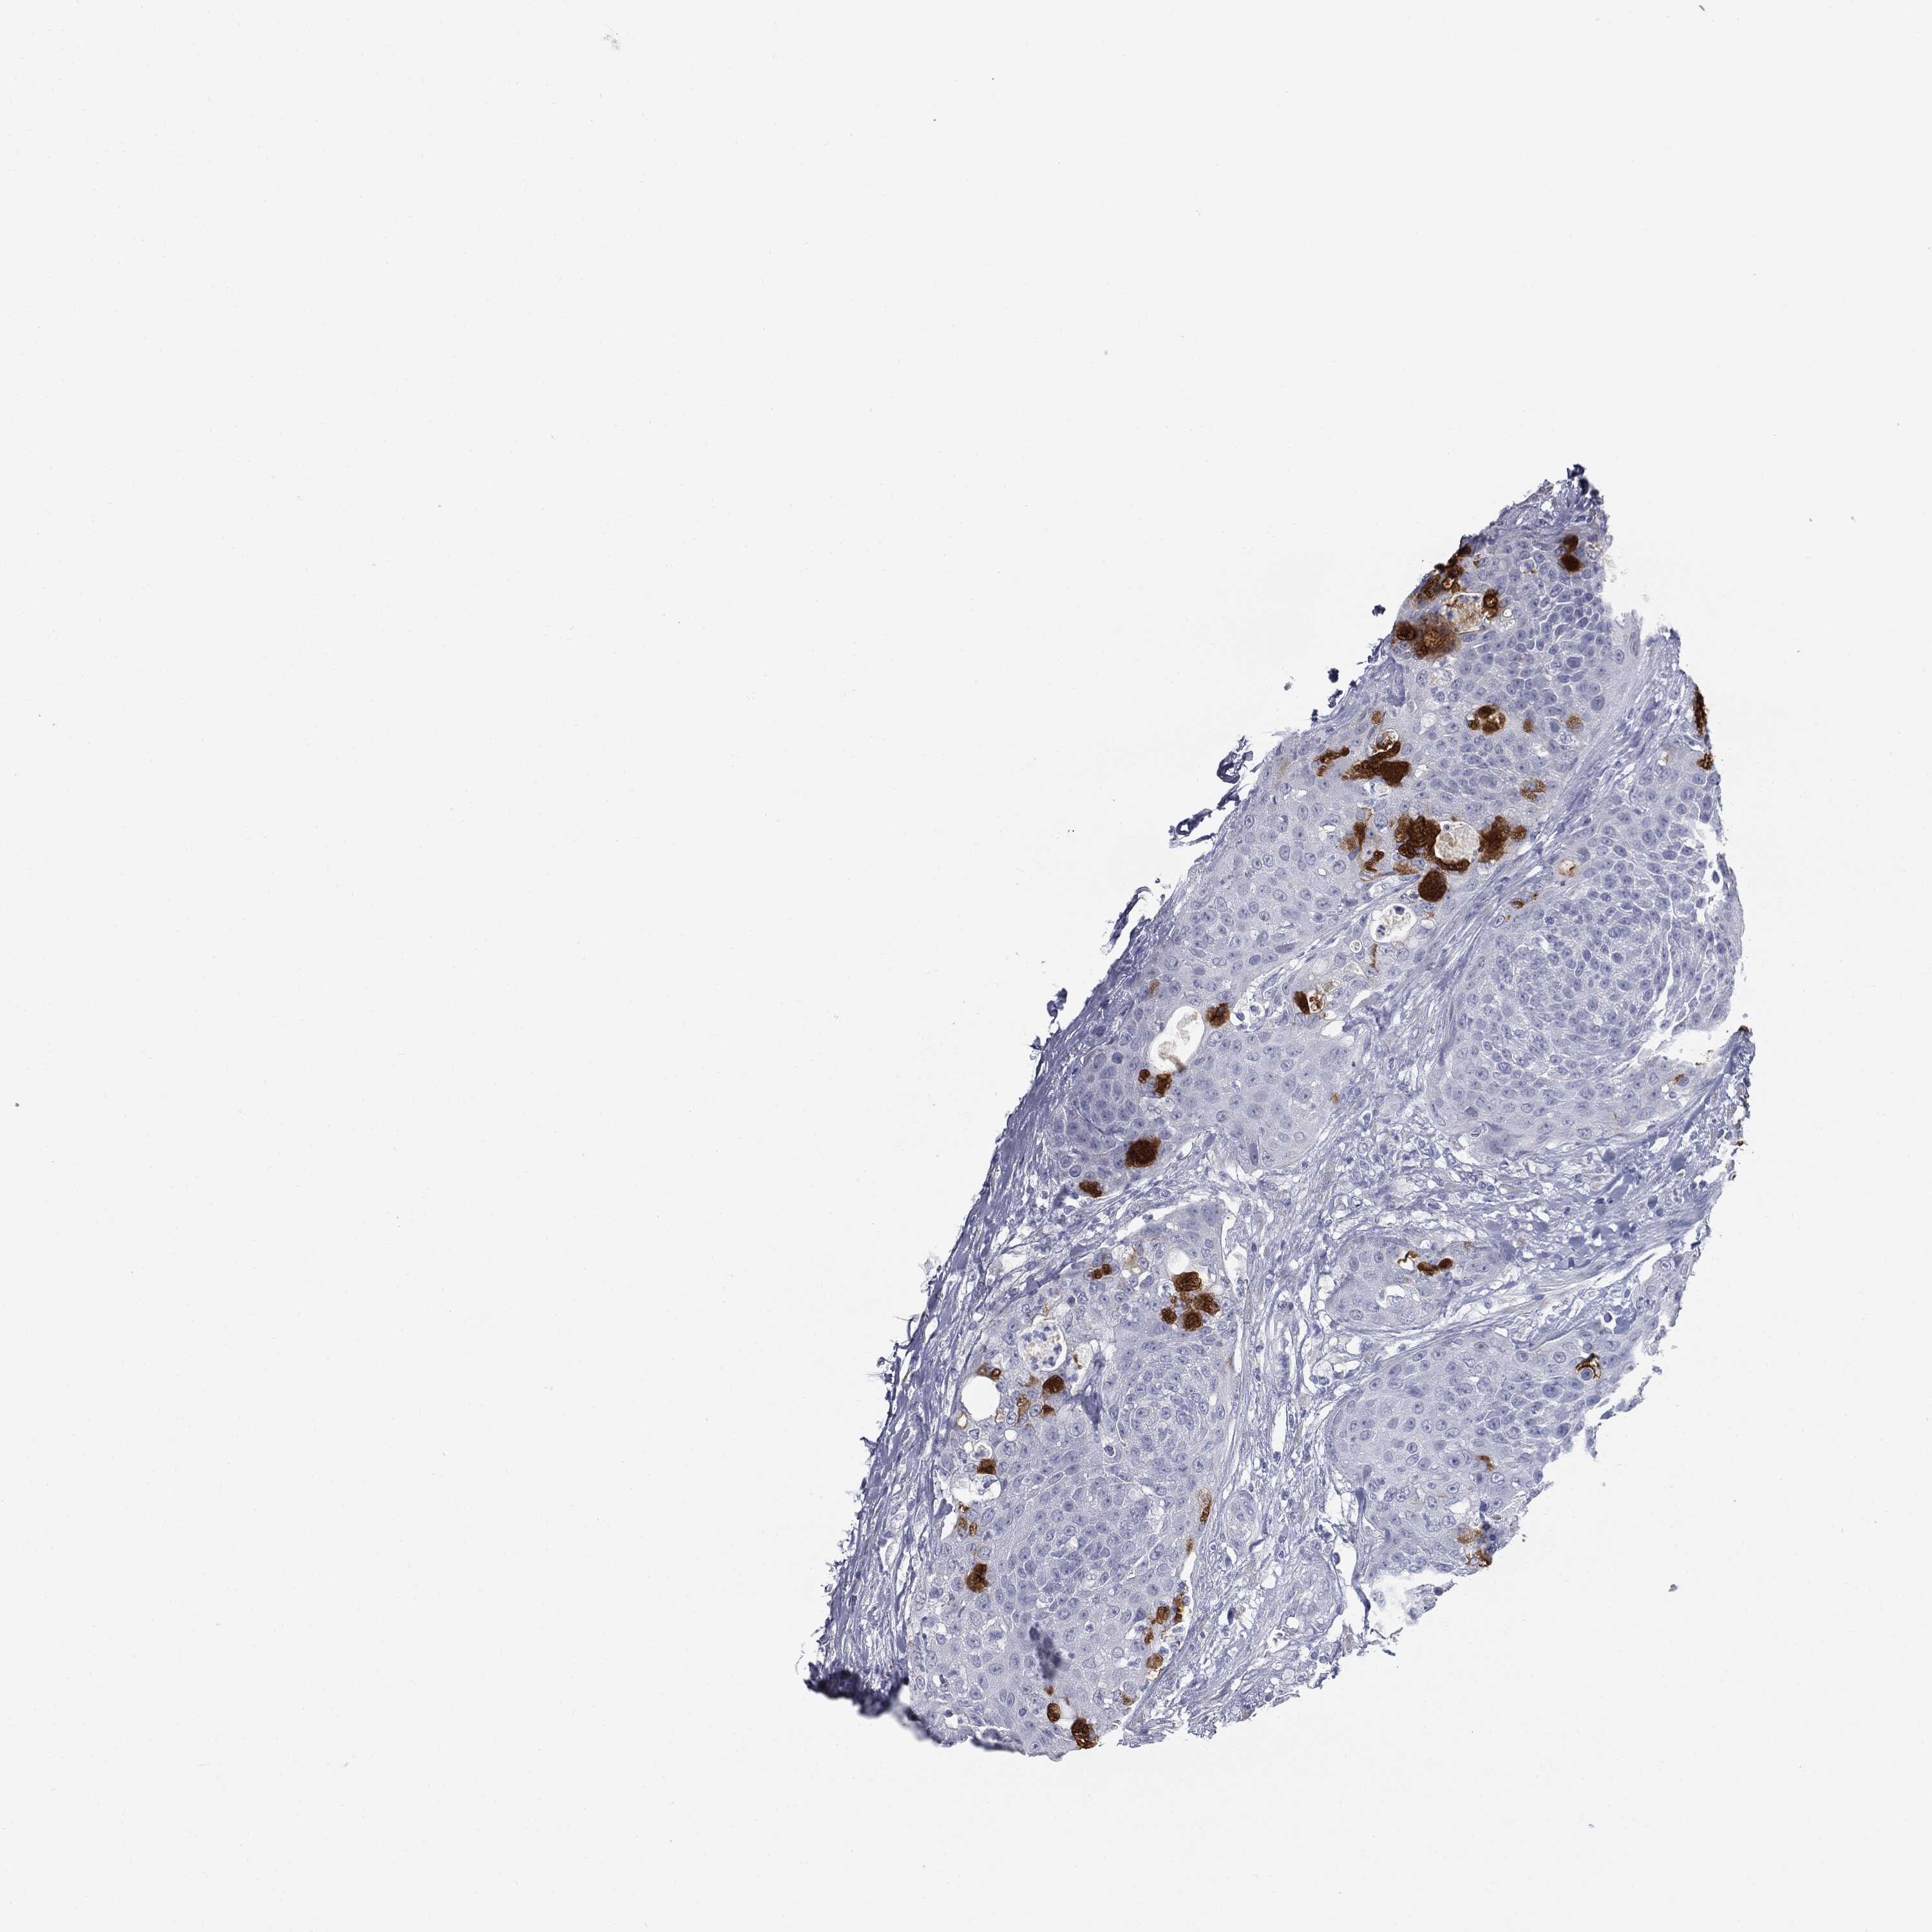

UROTHELIAL CANCER - Protein expressioni

A mouse-over function shows sample information and annotation data. Click on an image to view it in a full screen mode. Samples can be filtered based on level of antibody staining by selecting one or several of the following categories: high, medium, low and not detected. The assay and annotation is described here.

Note that samples used for immunohistochemistry by the Human Protein Atlas do not correspond to samples in the TCGA dataset.

Antibody stainingi

Antibody staining in the annotated cell types in the current human tissue is reported as not detected, low, medium, or high, based on conventional immunohistochemistry profiling in selected tissues. This score is based on the combination of the staining intensity and fraction of stained cells.

Each image is clickable and will lead to virtual microscopy that enables deeper exploration of all samples and also displays staining intensity scores, fraction scores and subcellular localization as well as patient and tissue information for each sample.

Urothelial carcinoma, High grade

Urothelial carcinoma, NOS

Urothelial carcinoma, Low grade

Adenocarcinoma, NOS